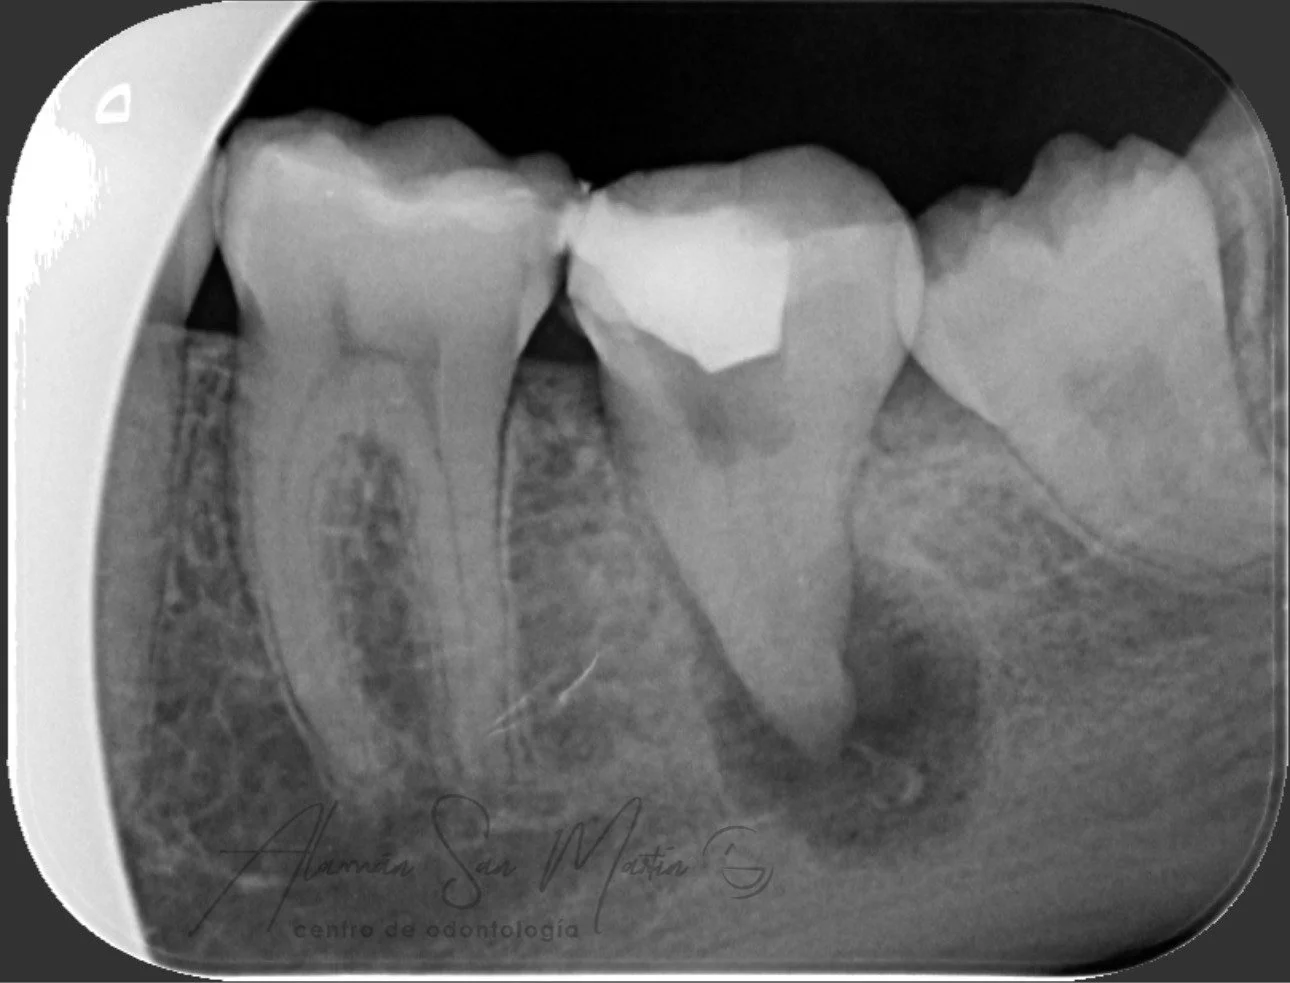

La Endodoncia consigue eliminar el nervio de los dientes con dolor por caries o algún traumatismo y rellenarlo con material biocompatible, conservando el diente sin tener que extraerlo.

En nuestra clínica se realizan endodoncias por un Especialista En Endodoncia tratando desde casos sencillos a casos complejos de retratamientos o fracasos en endodoncias antiguas.

Utilizamos técnicas avanzadas de diagnóstico en endodoncia como la Radiovisiografía Digital, el Localizador de Ápice y Técnicas Rotatorias de instrumentación de los conductos radiculares, utilizando el microscopio en los pacientes que lo requieren.